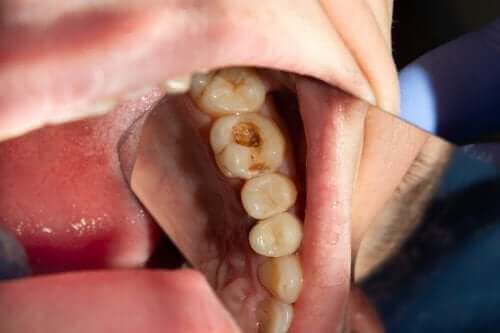

Οι κοιλότητες ξεκινούν ως λευκά σημάδια με αλευρώδη υφή που εμφανίζεται στα δόντια εξαιτίας του αδυνατίσματος και της αποδυνάμωσης του σμάλτου. Αν συνεχίζεται η απώλεια μετάλλων, η πάθηση θα χειροτερεύσει και κάνει την εμφάνισή της μια μαυρο-κίτρινη κοιλότητα.

Όσο επιδεινώνεται η κατάσταση της κοιλότητας, η τερηδόνα μπορεί να χωρίσει το δόντι στα δύο. Μόλις φτάσει στην οδοντίνη, το δόντι θα γίνει πιο ευαίσθητο στο κρύο, τη ζέστη και τα γλυκά φαγητά. Όταν συμβεί αυτό, έρχεται η ώρα για σφράγισμα.